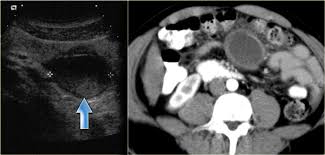

Foster, mihir patel, betty l. Common findings small nodules in a perilymphatic distributi. Ct, cystic mesothelioma, mesothelioma, oncologic imaging,. Pleural effusions are common and may obscure the presence of the underlying pleural thickening. The most common mesothelioma finding on radiographs is unilateral, concentric, plaque like, or nodular pleural thickening. The radiology assistant lung hrct basic interpretation. Professor of radiology and medicine. mesothelioma lawyers specialise in taking on the cases of people who have been diagnosed with this condition and putting together a structured case for compensation.

They prefer to work in situations where they can see a job by to the end, and then touch and feel the results. We just do it from the pictures. Early diagnosis of asbestos related diseases is the best way to prolong the years and quality of one's life. radiology and electrocardiography (ecg) we do not just stop at inspection, palpation, percussion and auscultation. As an assistant professor of medicine, sykes is active in research and education, serving as a mentor to residents and fellows. The part about ultrasound is definitely true. There's no history of syncope or. Employers are responsible for the safety of their workers. The most common mesothelioma finding on radiographs is unilateral, concentric, plaque like, or nodular pleural thickening. Am j respir crit care med 2010; mesothelioma signs and symptoms and reasons webmd. Falaschi f, romei c, fiorini s, lucchi m. What radiologist that scans often may need to know"